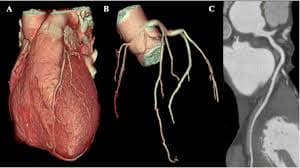

Coronary Angiogram

A CT Coronary Angiogram is a non-invasive imaging test that uses a CT scanner, and contrast dye to create detailed 3D pictures of your heart's arteries, revealing plaque, blockages, or narrowing (stenosis) that can cause heart problems like chest pain.

3D Vessel Analysis

CORONARY ASSESSMENT

- •Non-invasive coronary artery evaluation

- •Stenosis and blockage detection